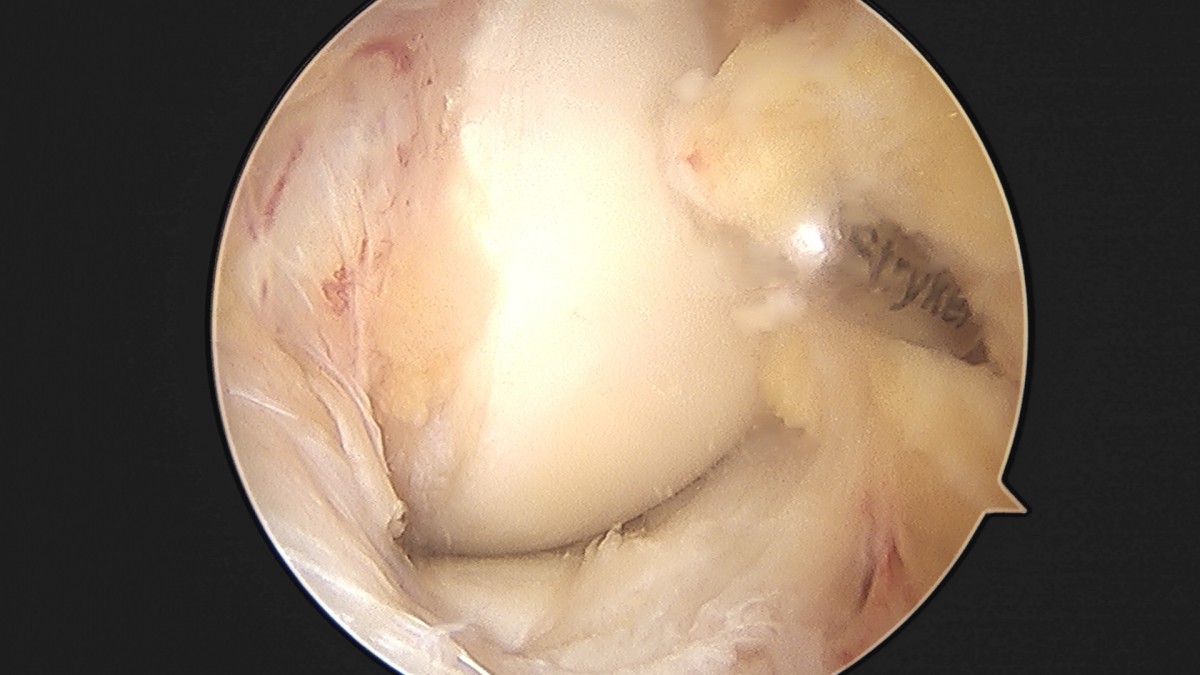

이재상원장님 무릎 반월상 연골판 절제술 조미O 환자

dae765e4d9ac96aee867c9d6292d8784_1758005941_265.jpg